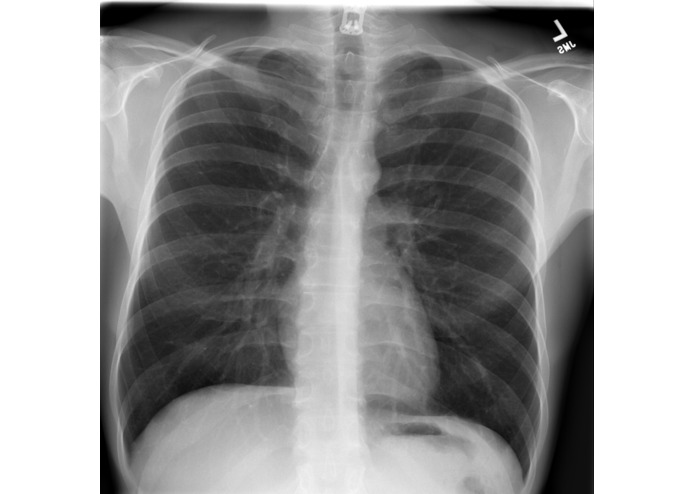

Trained a DenseNet121 Deep learning architecture on a Dataset of 112,120 frontal-view X-rays. The network was configured in PyTorch Python and trained on a Rutgers University GPU Cluster . The Web Dev is done in Django python to create a platform for professionals to share it with others.

An amazing average accuracy of 85.0846 on the test set trained on a 121 layer Dense CNN.